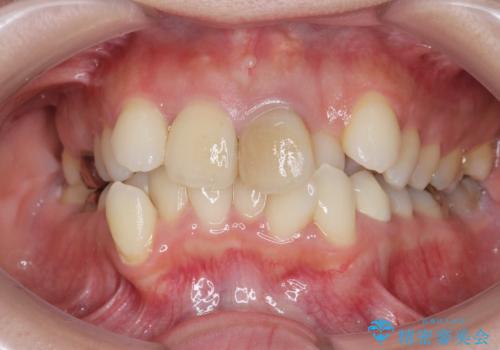

X線写真より、充填剤の突き出た状態の根管治療の再治療を行い、セラミック治療を計画すると同時に、

歯ブラシがしづらく虫歯の原因となっている歯の位置の悪い右上側切歯の抜去を行います。

清掃を難しくしている歯を抜去することで虫歯の再発を防ぐような治療方針としました。